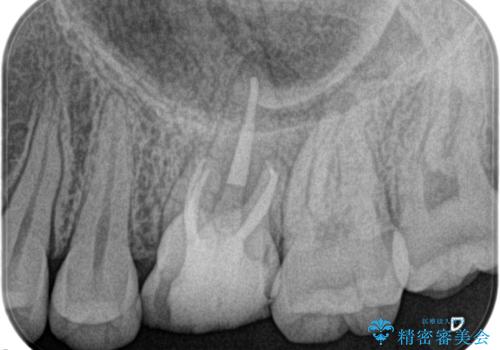

奥歯の根管治療

担当医 河口智英